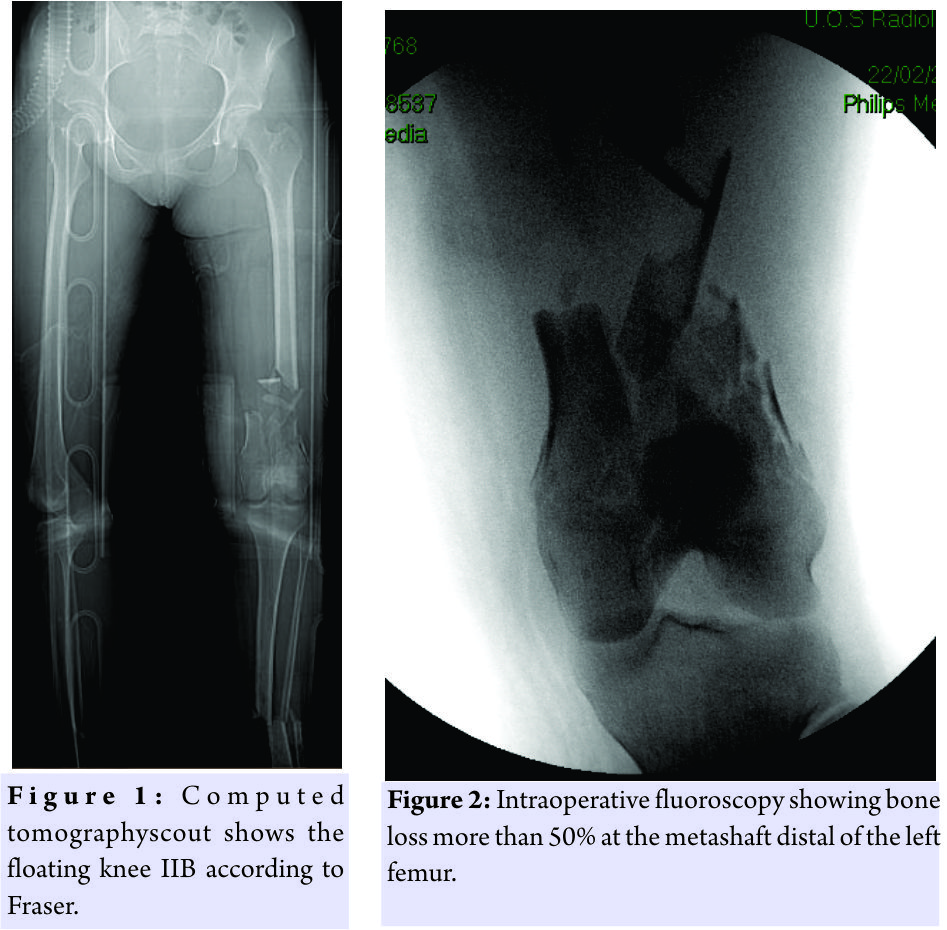

At 4:30 am, a 23-year-old patient arrived at our drug enforcement administration, after a high kinetic energy car accident (car against the wall) in orotracheal intubation with a Glasgow coma scale (GCS) of 11/15, mangled extremity severity score 4 points for the femur, and 3 points for the leg, and an injury severity score of 24 points:oderate concussion, moderate splenic ulcerations, supra-intercondylar fracture of the femur (3.3-C1 according to AO) left exposed Gustilo Anderson (GA) IIIB and bone loss of the metaphyseal area >50% and shaft fracture(Fig.1 and 2) with a third fragment (4.2-B2 according to AO) exposed GA 3B(Fig.1). The patient was treated in emergency with a bridge femorotibial external fixator after extensive cleaning and debridement of open fractures(Fig.3a and b). After stabilization, the wounds were covered with iodine-impregnated incision drape (Ioban). During the damage control’s operations, a fragment of 8 cm × 3 cm × 4cm of bone substance corticospongiosa was found in the left sock. The fragment was immersed in a solution of cefuroxime, gentamicin, and metronidazole and maintained at a temperature of −3°C until 2h before the intervention because it was irradiated with a dose of 25kGy. The 4days, we removed the antibiotated chains and the Ioban cover which were replaced with vacuum therapy. The patient never had fever over 38°Cduring his 10 days in intensive care and in the ward. The delayed risk of tibial consolidation was equal to 8 of 10 according to A.R.R.C.O. As regards the femur, the risk of non-union of the fracture of the femur of 51 points according to the non-union scoring system(N.U.S.S).